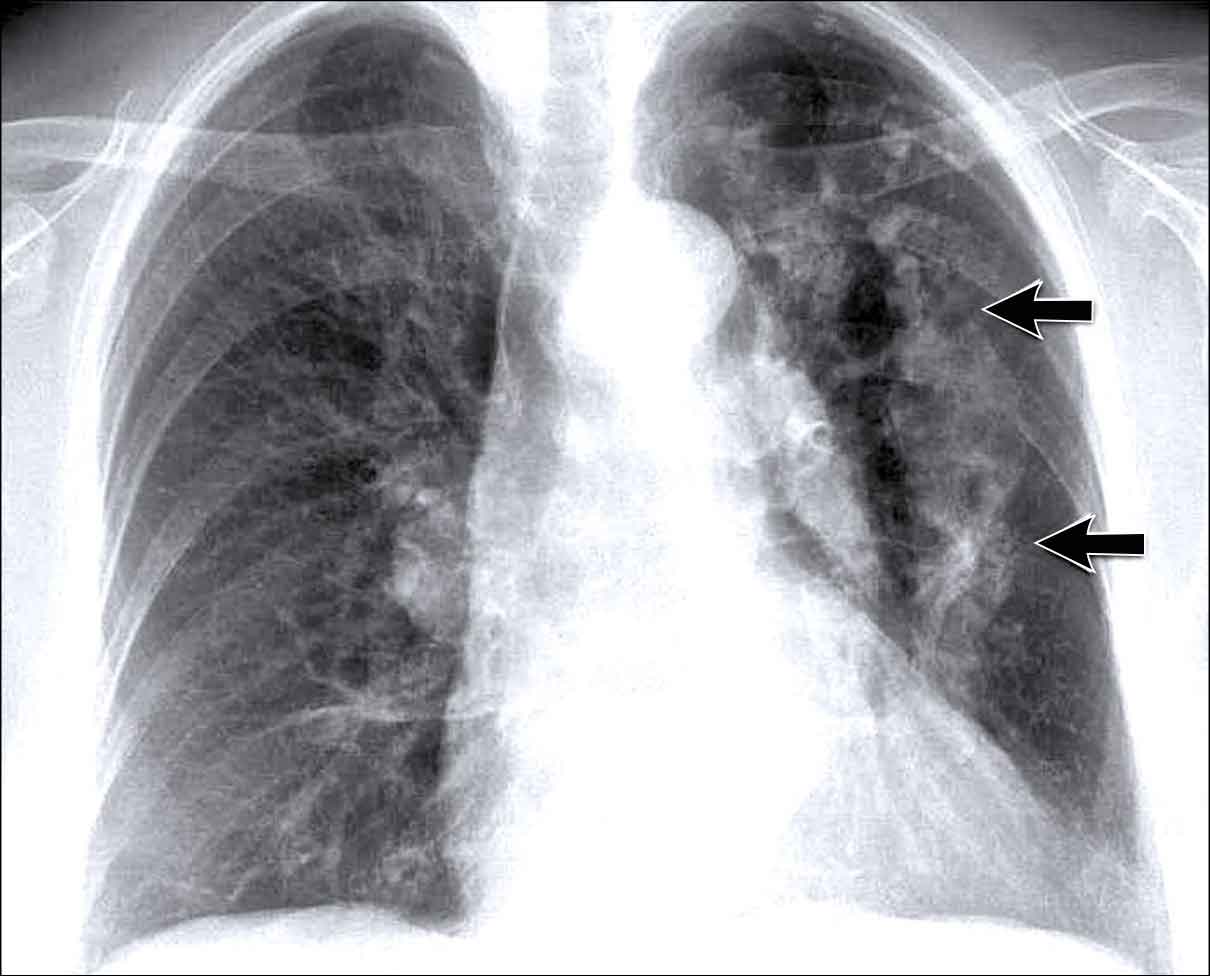

Hidden area (5): Mass Behind the First Rib

In some patients, an accessory joint at the anterior aspect of the first rib may simulate a mass, as we learned earlier.

However this area is also a "hidden zone", where true lesions can be masked.

• In this case, a small lung carcinoma was obscured by the left first rib on the PA view.

• On the lateral film, the lesion is visible in the retrosternal space.

Continue with the PET-CT...

Subsequent PET-CT imaging confirmed a hypermetabolic tumor (arrow), with metastases to the bone and liver.

• Diagnosis was confirmed via biopsy of an osteolytic metastasis in the iliac bone.